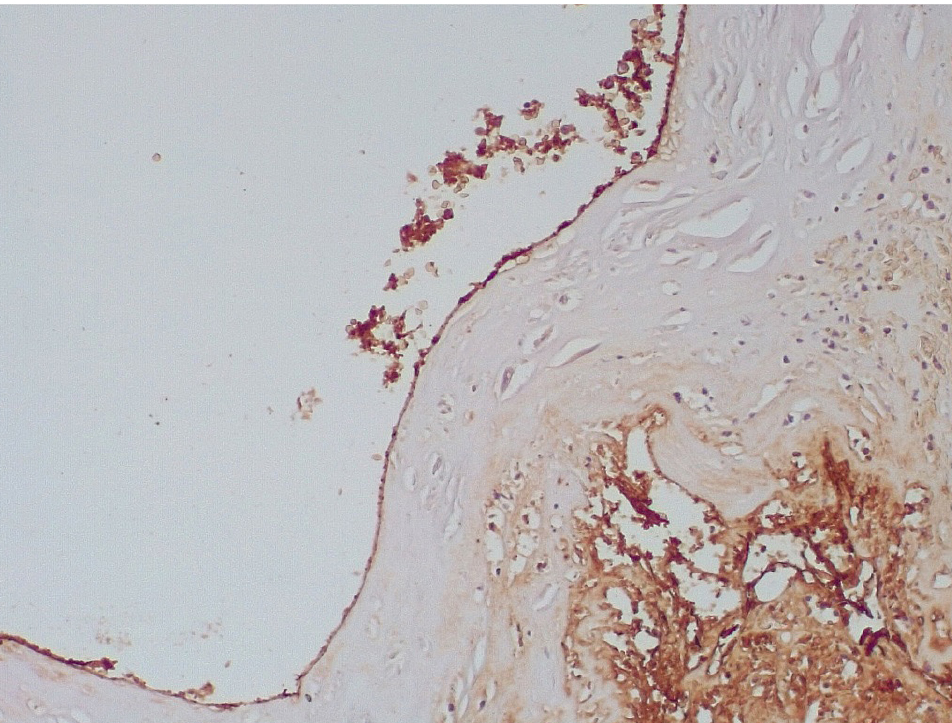

Обращало внимание, что в местах «оголенного» эндотелия КА отмечалась слабая экспрессия белка CD31, что указывало на выраженные дистрофические и некробиотические изменения клеток (рис. 2). При этом экспрессия ФВ была яркой, выраженной на всем протяжении интимы КА (рис. 3).

Рис. 3. Гиперэкспрессия ФВ в клетках эндотелия КА (1–3-и сутки). Иммуногистохимическое исследование с антителами к vWF. Ув. ×200

Маркер эндотелиальной дисфункции – фактор Виллебранда (ФВ) ярко экспрессировался в клетках эндотелия КА и субинтимально, что могло свидетельствовать о выраженной дисрегуляции коагуляционных свойств крови (рис. 5). В то же время экспрессия белка CD31 в указанные сроки после стентирования была слабовыраженной, что могло указывать на выраженные дистрофические изменения эндотелиальных клеток КА.

Рис. 5. Яркая экспрессия белка ФВ в клетках эндотелия, субинтимальных отделах КА (3–7-е сутки). Иммуногистохимическое исследование с антителами к vWF. Ув. ×200